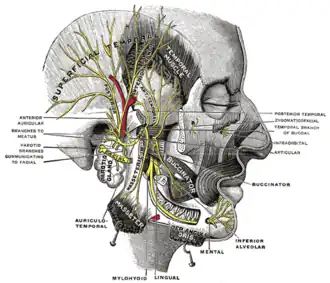

Mandibular division of the trifacial nerve

Mandibular division of the trifacial nerve -